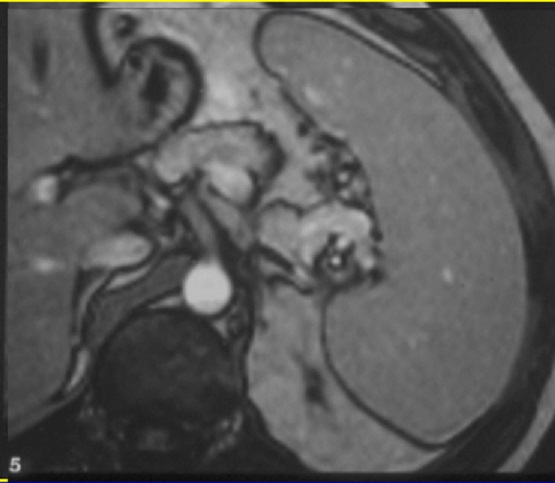

-La IRM : Methode le plus frequemment d’utilise pour

etudie la rate et se donne des images de la rate en bonne definition . L’examen doit

realise a jeune afin de diminue de artefact des mouvements

peristaltismes gastroduodenal . La maladie en decubitus

dorsale , parametre choisir en fonction du patient , de

l'orientation clinique et par la caracteristique des lesions

de organe etudie . La sequece ponderee sur T1 , T2 rapide en

apnee ( HASTE ), T2 FATSAT et avec injection de chelate de

Gadolinium intraveineuse seront intallees. Image

radiologique IRM normale de la rate

-

Les sequences de

image en ponderation T1 sont fondamentales et

frequemment utilise pour explorer le parenchyme

de la rate . En ponderation T1 sur les sequences de

saturation de graisse ( FAT SAT ) le parenchyme de la

rate est homogene et intermediaire de intensite , ce la legerement hyperintense que les autre organe et moins

intense que le foie

image en ponderation T2 la rate est hyperintense

L’injection de

chelates de gadolium est necessite de explorer le temps

de rehaussement parenchymateuse tres precoce ( 15-25 sec

apres l’injection ) avec aspect de la rate heterogene et

puis rapidement devient homogene et isointense en

rapport avec le foie a la fin du temps de evacuation .

Image

radiologique IRM ponderee T1 de la rate avec aspect

parenchymateuse homogene et leregemant moins

intensite que le foie |

|

Aspect radiologique IRM de

la rate pondere sur T2 FatSat . La parenchyme de la

rate est homogène et tres hypersignal que le foie et

les autres organes . Image IRM T2 FATSAT coupe axial |

Aspect de la rate au temps de evacuation

apres injection de chelate de Gadolinium . Le

parenchyme de la rate est homogene et isosignal par

rapport au foie |